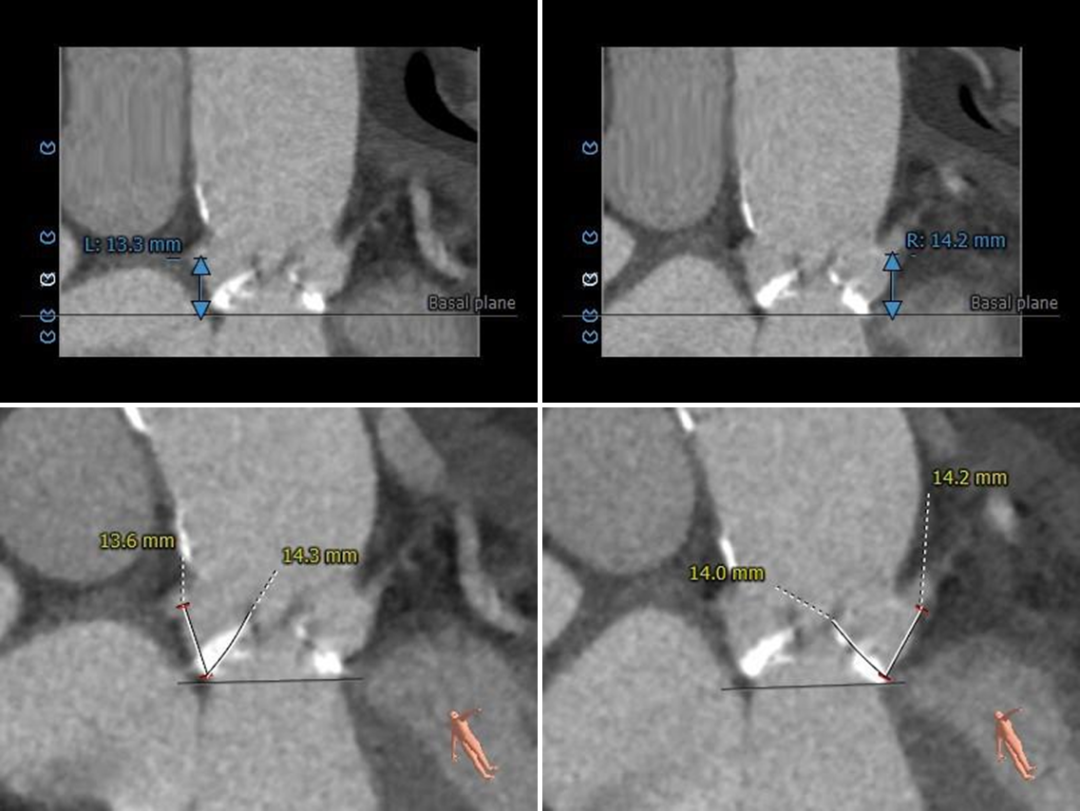

根部测量

瓣环平均径24.6mm,STJ、升主内径可,非横位心

冠脉测量

冠脉开口高度可,切线位测量左窦瓣叶略长于左冠开口